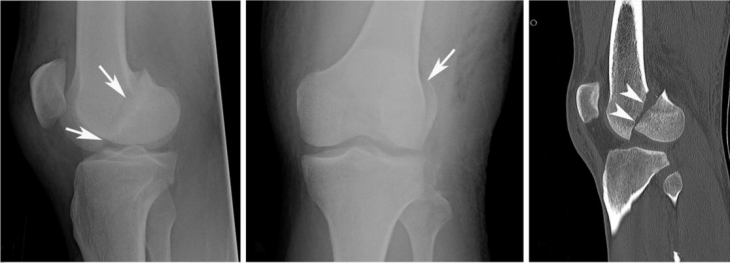

Hoffa骨折是一种罕见的局限于股骨髁冠状面的骨折,占股骨远端骨折的8.7%--13%。其中外髁较内髁、双髁多,占整个Hoffa骨折的78--85%。

由于临床上此种骨折较少见,加之特殊的解剖特点,骨折极不稳定,诊断困难,容易漏诊,且并发症多,此前的认识和治疗也较模糊、不全面。近年来,随着交通伤患者人数的增加,该骨折的发病率也呈现出明显的上升趋势。

Hoffa骨折多为高能量损伤,青壮年多见。损伤机制多为膝关节屈曲时,轴向剪力作用于股骨髁后部所致。屈膝内翻或外翻情况下紧急制动,自股骨近端传导的轴向暴力作用于股骨髁,同时来自胫骨远端的暴力传导至胫骨平台,使股骨髁与胫骨平台之间产生巨大的剪切力,从而导致Hoffa骨折。常见于车祸伤、高处坠落伤。

当高能量暴力作用于股骨远端时,由于股骨远端存在外翻角的解剖特点,往往首先作用于外侧髁,因此,外髁Hoffa骨折明显多于内髁Hoffa骨折。